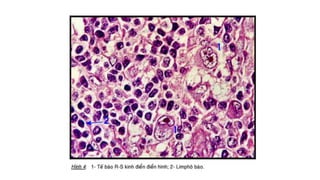

Tế bào Reed-Sternberg

- TB ác tính đặc trưng của bệnh

Hodgkin.

- Kt lớn 20-50µm.

- Bào tương rộng.

- Nhân lớn

- Chất nhiễm sắc thô vón và tập

trung sát màng nhân.

- Hạt nhân to và ưa toan

- Hình ảnh “soi gương”, mắt cú”

• #34 Hình 1: Tế bào Reed-Sternberg Là những tế bào ác tính đặc trưng của bệnh Hodgkin, đặc hiệu để chẩn đoán bệnh Hodgkin. Tế bào Reed-Sternberg điển hình có kích thước lớn 20-50µm hoặc hơn. Bào tương rộng, thuần nhất hoặc dạng hạt, ưa toan nhẹ. Nhân lớn. Kích thước thay đổi, màng nhân dày, chất nhiễm sắc thô vón và tập trung sát màng nhân. Hạt nhân rất to, ưa toan, nằm giữa nhân và tách biệt với chất nhiễm sắc tạo nên một quầng sáng quanh hạt nhân. Ðôi khi thấy tế bào hai nhân đối xứng với nhau tạo nên hình ảnh “soi gương” hay “mắt cú”. Những tế bào lớn, một nhân nhưng nhân không có múi, hạt nhân nổi rõ gọi là tế bào Hodgkin hoặc tế bào dạng Sternberg. Nguồn gốc của tế bào Reed-Sternberg và các biến thể của nó là những nguyên bào lympho phát triển từ các tế bào Th. Hình 2: Tế bào Reed-Sternberg; hình ảnh cho thấy lymphocytes bình thường so với một tế bào Reed-Sternberg, có kích thước lớn, bất thường lymphocytes có thể chứa nhiều hơn một hạt nhân. Những tế bào này được tìm thấy trong u lymphô Hodgkin

• #35 Hình 1: Tế bào RS cổ điển Hình 2: TB khuyết Hình 3: TB bắp rang